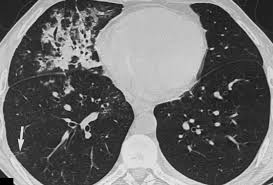

Pulmonary Embolism: What Patients and Clinicians Should Know

Introduction Pulmonary embolism is a potentially life‑threatening condition and a priority for emergency and preventive healthcare. Understanding its causes, symptoms and pathways to diagnosis matters for clinicians, hospital administrators and members of the public alike. Timely recognition and treatment can markedly reduce complications and mortality, while effective prevention reduces hospital stay and long‑term disability. Main […]